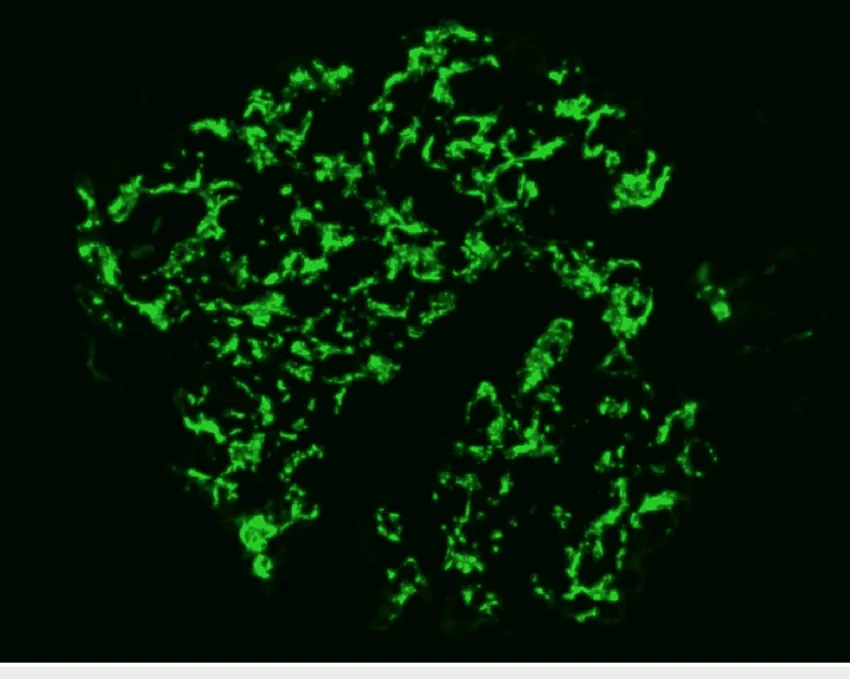

A glomerulonefrite por C3 (GNC3) resulta de ativação descontrolada da via alternativa do complemento e pode simular uma GN pós-infecciosa. O diagnóstico correto depende do reconhecimento do padrão de deposição de C3 e da investigação genética. Com terapias-alvo como o eculizumabe e o iptacopan, identificar precocemente a GNC3 pode mudar o desfecho do paciente.